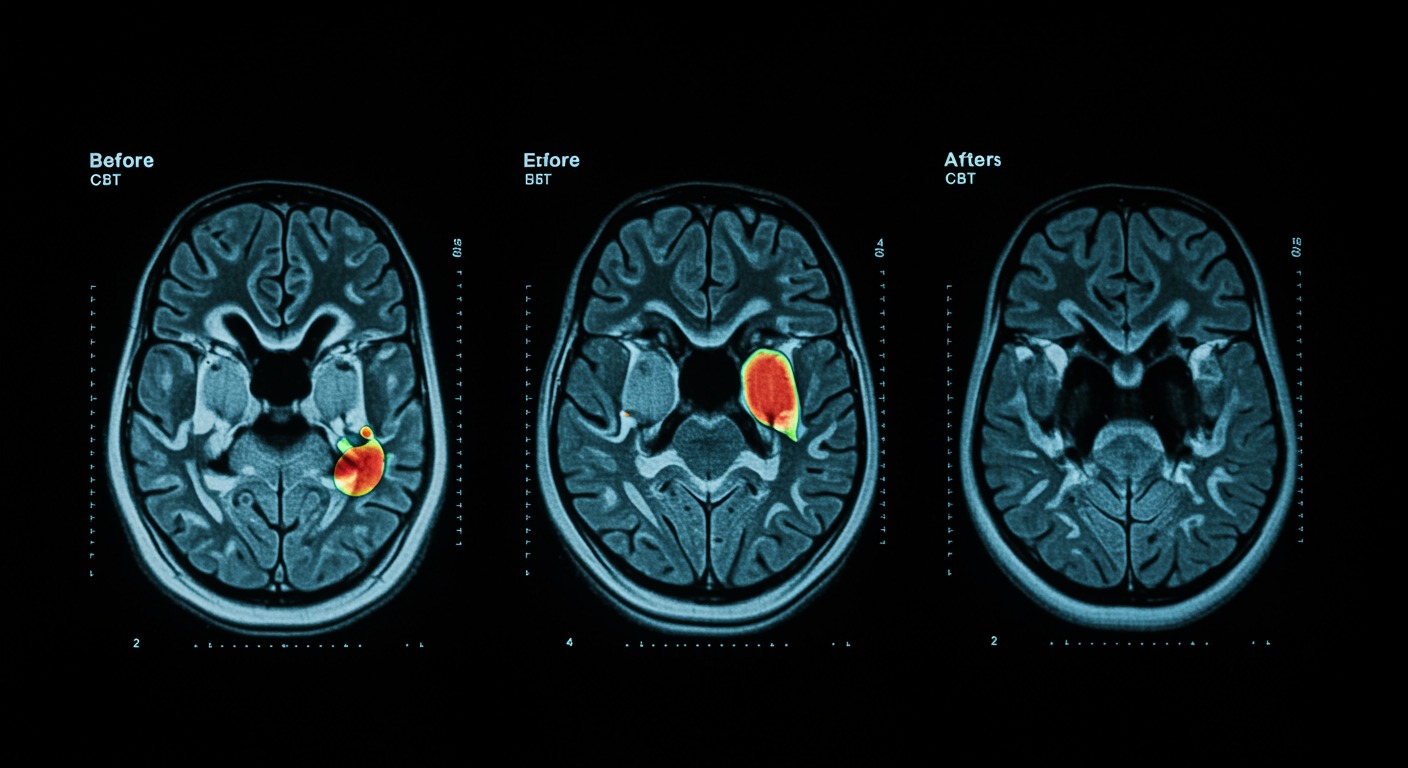

How does CBT change the depressed brain?

Yes. Cognitive behavioral therapy measurably changes brain activity in limbic, striatal, cingulate, and frontal areas, partially normalizing neural patterns associated with depression and reducing negative cognitive biases. A systematic review of 14 task-based fMRI studies published in the Journal of Affective Disorders shows that CBT produces objective, measurable neurobiological changes that correlate with symptom improvement.

This systematic review provides the neurobiological proof that CBT isn’t just “talk therapy” - it’s literally rewiring the brain. The fact that we can see measurable changes in limbic, striatal, cingulate, and frontal areas on fMRI scans is remarkable. These are exactly the brain regions we know are dysfunctional in depression. The limbic system processes emotions, the striatum is involved in motivation and reward, the cingulate cortex handles attention and emotion regulation, and the frontal areas manage executive function and decision-making. CBT is essentially teaching the brain new ways to process information and emotions, and we can now see this happening in real-time through brain imaging.

This systematic review analyzed longitudinal fMRI studies examining brain activity changes in depressive patients undergoing cognitive behavioral therapy. The researchers focused on task-based fMRI studies that measured brain function before and after CBT treatment, allowing them to identify specific neural changes associated with therapeutic improvement. The review examined changes across multiple brain regions and their relationship to symptom remission.

- Understand that CBT produces measurable, objective changes in brain function that can be seen on fMRI scans

- Recognize that CBT works by normalizing abnormal brain activity patterns in key regions involved in emotion and cognition